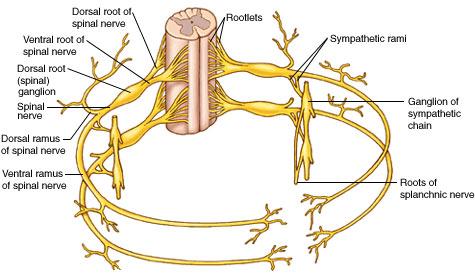

What forms a spinal nerve?

a dorsal root and a ventral root

What type of fibers does a dorsal root contain?

afferent/sensory fibers

What type of fibers does a ventral root contain?

efferent/motor fibers

A spinal nerve bifurcates into a _______ and a ________

dorsal ramus and ventral ramus

classified by impulse direction, a dorsal ramus or ventral ramus is which type of nerve?

mixed nerve